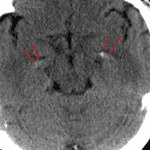

Choroid Plexus in the Temporal Horns

Mimicking Subarachnoid Hemorrhage

Findings Relating to the Mimic

- Areas of high density within the temporal horns of the lateral ventricles bilaterally, which have attenuation values up to 150 Hounsfield units compatible with physiologic calcifications of the choroid plexus in these regions.

Discussion

- Usually choroid is easy to differentiate from hemorrhage given the characteristic location and physiologic calcification. Using bone windows and measuring point value attenuation may help you confidently identify calcification associated with choroid.

- Choroid plexus is also found in the foramina of Luschka, along the posterior medullary velum of the fourth ventricle, and along the roof of the third ventricle.